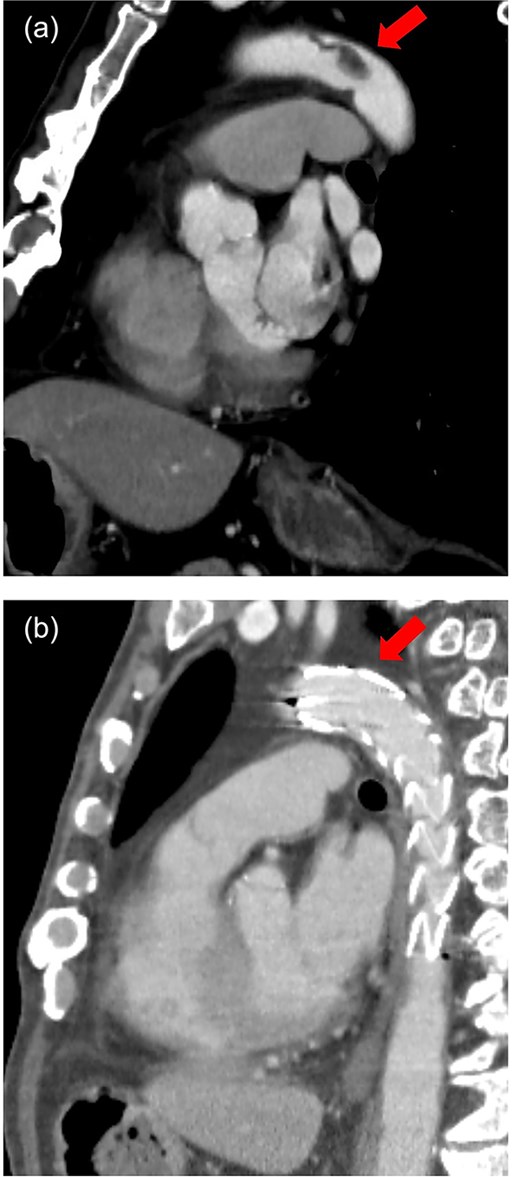

The patient was a 78-year-old man who had been hospitalized at a prior institution for Tolosa-Hunt syndrome, a rare inflammatory condition causing orbital pain. He had undergone steroid pulse therapy and was maintained on oral prednisolone (40 mg daily). He was also receiving medical treatment for diabetes mellitus, with an HbA1c level of 7.9%. The patient presented with complaints of left leg discomfort and weakness. Contrast-enhanced CT revealed poor perfusion distal to the left common iliac artery, leading to a diagnosis of ALI. He was subsequently transferred to our surgical department for further evaluation and treatment. On arrival, physical examination revealed coldness in the left lower limb, with absent palpable pulses in the dorsalis pedis and posterior tibial arteries. Doppler ultrasonography confirmed the absence of arterial flow in the left lower extremity, consistent with critical ischemia. The patient's electrocardiogram showed sinus rhythm. A review of CT imaging showed thrombotic occlusion extending from the left common femoral artery (CFA) to the superficial femoral artery, with poor perfusion distal to the popliteal artery (Video 1) (Fig. 1). Additionally, a filling defect was identified in the distal aortic arch, consistent with a thrombus (Fig. 2a). The thrombus appeared pedunculated and was attached to the lesser curvature of the descending thoracic aorta distal to the left subclavian artery. It was considered highly mobile, posing a significant risk of embolization. No evidence of intracardiac thrombi was observed, and the DTAT was identified as the likely embolic source responsible for the ALI. Given the urgency of salvaging the ischemic limb, thrombus retrieval was prioritized, while simultaneous management of the embolic source was deemed equally critical to prevent recurrence. Open surgery was considered high-risk due to the patient’s age, diabetes, and chronic steroid use. As a less invasive alternative, we opted for TEVAR to immobilize the floating thrombus. During the procedure, bilateral CFAs were surgically exposed to provide access and enable immediate removal of the embolic source if needed. A transesophageal echocardiogram (TEE) revealed a highly mobile intra-aortic thrombus (Video 2). A 26× 26 × 150 mm stent graft (Valiant Captivia Thoracic Stent Graft; Medtronic, Santa Rosa, CA, USA) was deployed just distal to the left subclavian artery under fluoroscopic guidance. Real-time TEE guidance ensured continuous monitoring of the floating thrombus and confirmed no embolization during intravascular manipulation. Following stent graft deployment, thrombus retrieval was performed via the left CFA using a 4-Fr Fogarty catheter (Fogarty Fortis arterial embolectomy catheter; Edwards Lifesciences, Irvine, CA, USA), successfully retrieving fibrin thrombi. Intraoperative angiography demonstrated restored blood flow in the lower extremity, with improved perfusion extending to the foot. Pulses in the dorsalis pedis and posterior tibial arteries were palpably restored bilaterally. The patient was extubated in the operating room and progressed without any findings suggestive of intestinal or lower extremity ischemia. Postoperative CT confirmed successful exclusion of the aortic thrombus (Fig. 2b) and restoration of adequate lower limb perfusion (Fig. 3). The patient was initiated on oral anticoagulation therapy with edoxaban 30 mg to prevent future thrombus formation and experienced an uneventful recovery. This patient has remained free of recurrent embolic events and has shown stable progress post-procedure.

Sagittal view of contrast-enhanced CT. (a) Preoperative. A pedunculated intra-aortic thrombus is attached to the distal arch. (b) Postoperative. Thoracic stent graft is implanted in the distal arch with successful exclusion of the aortic thrombus.